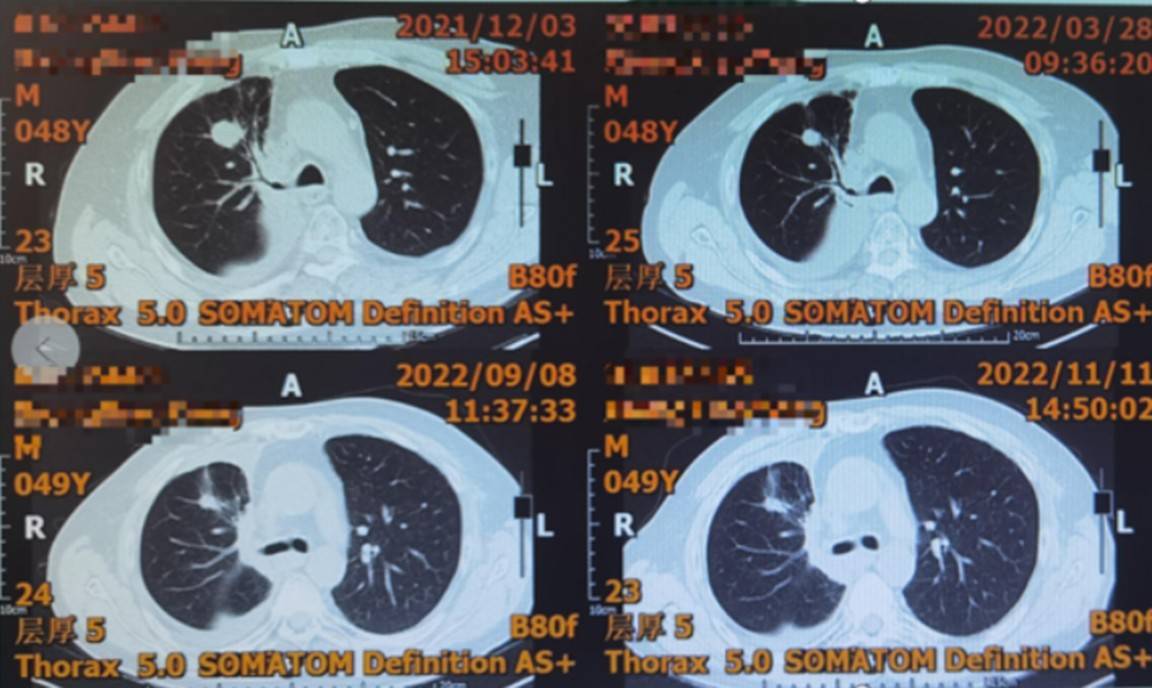

疗效评价:治疗期间每8周(48周后每12周)进行一次肿瘤评估。2022年3月30日首次评估即达到部分缓解(PR)(图1),靶病灶合计从筛选期的55.5mm缩小至39.7mm;后续多次评估持续维持PR或SD状态,病灶持续缩小并稳定控制,最佳疗效为PR(图2);2022年12月患者因感染新型冠状病毒暂停治疗,2023年1月6日复查示疾病进展(PD)。截至疾病进展,患者接受芦康沙妥珠单抗治疗时长超13个月,无进展生存期(PFS)达13个月,缓解持续时间(DoR)达9个月。